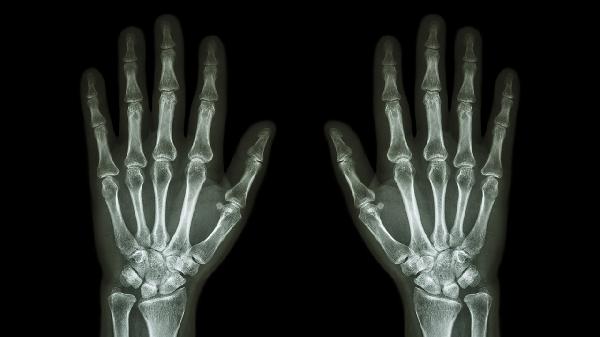

右手小拇指關(guān)節(jié)疼是怎么回事

右手小拇指關(guān)節(jié)疼可能與外傷、骨關(guān)節(jié)炎、腱鞘炎、痛風(fēng)性關(guān)節(jié)炎、類風(fēng)濕關(guān)節(jié)炎等因素有關(guān)??赏ㄟ^休息制動(dòng)、藥物治療、物理治療等方式緩解。

外力撞擊或過度使用可能導(dǎo)致小拇指關(guān)節(jié)周圍軟組織挫傷、韌帶拉傷甚至骨折。表現(xiàn)為局部腫脹、壓痛和活動(dòng)受限。急性期需立即冰敷并固定關(guān)節(jié),可遵醫(yī)囑使用云南白藥氣霧劑、雙氯芬酸鈉凝膠等外用藥物。若懷疑骨折需拍攝X線片明確診斷。